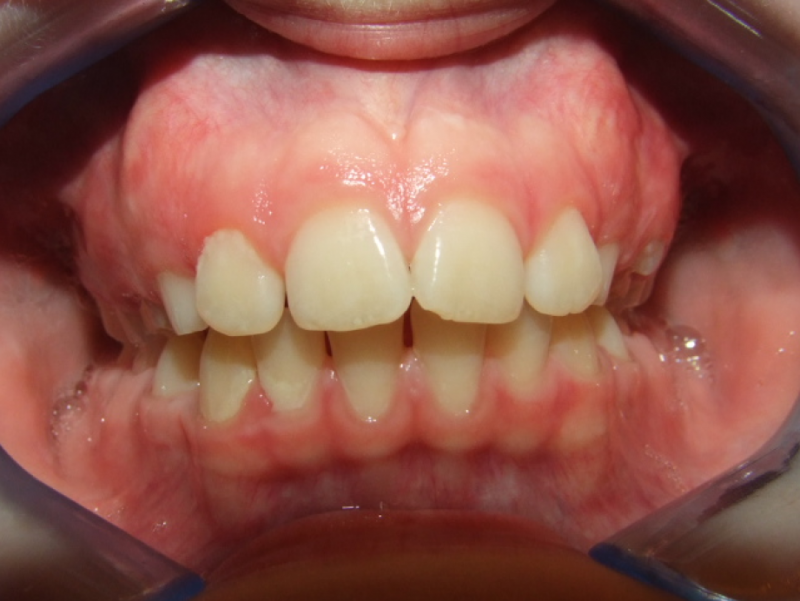

Behandeling Raoul

Duur

van 13-3-14 tot 16-9-15

Beschrijving

Leeftijd bij aanvang: 10 jaar

Bonded Hyrax + volledig vast onderkaak

Volledig vast bovenkaak + expander

Wrap + c-c bar onderkaak

Leeftijd bij afname: 12 jaar

Voor behandeling

Na behandeling